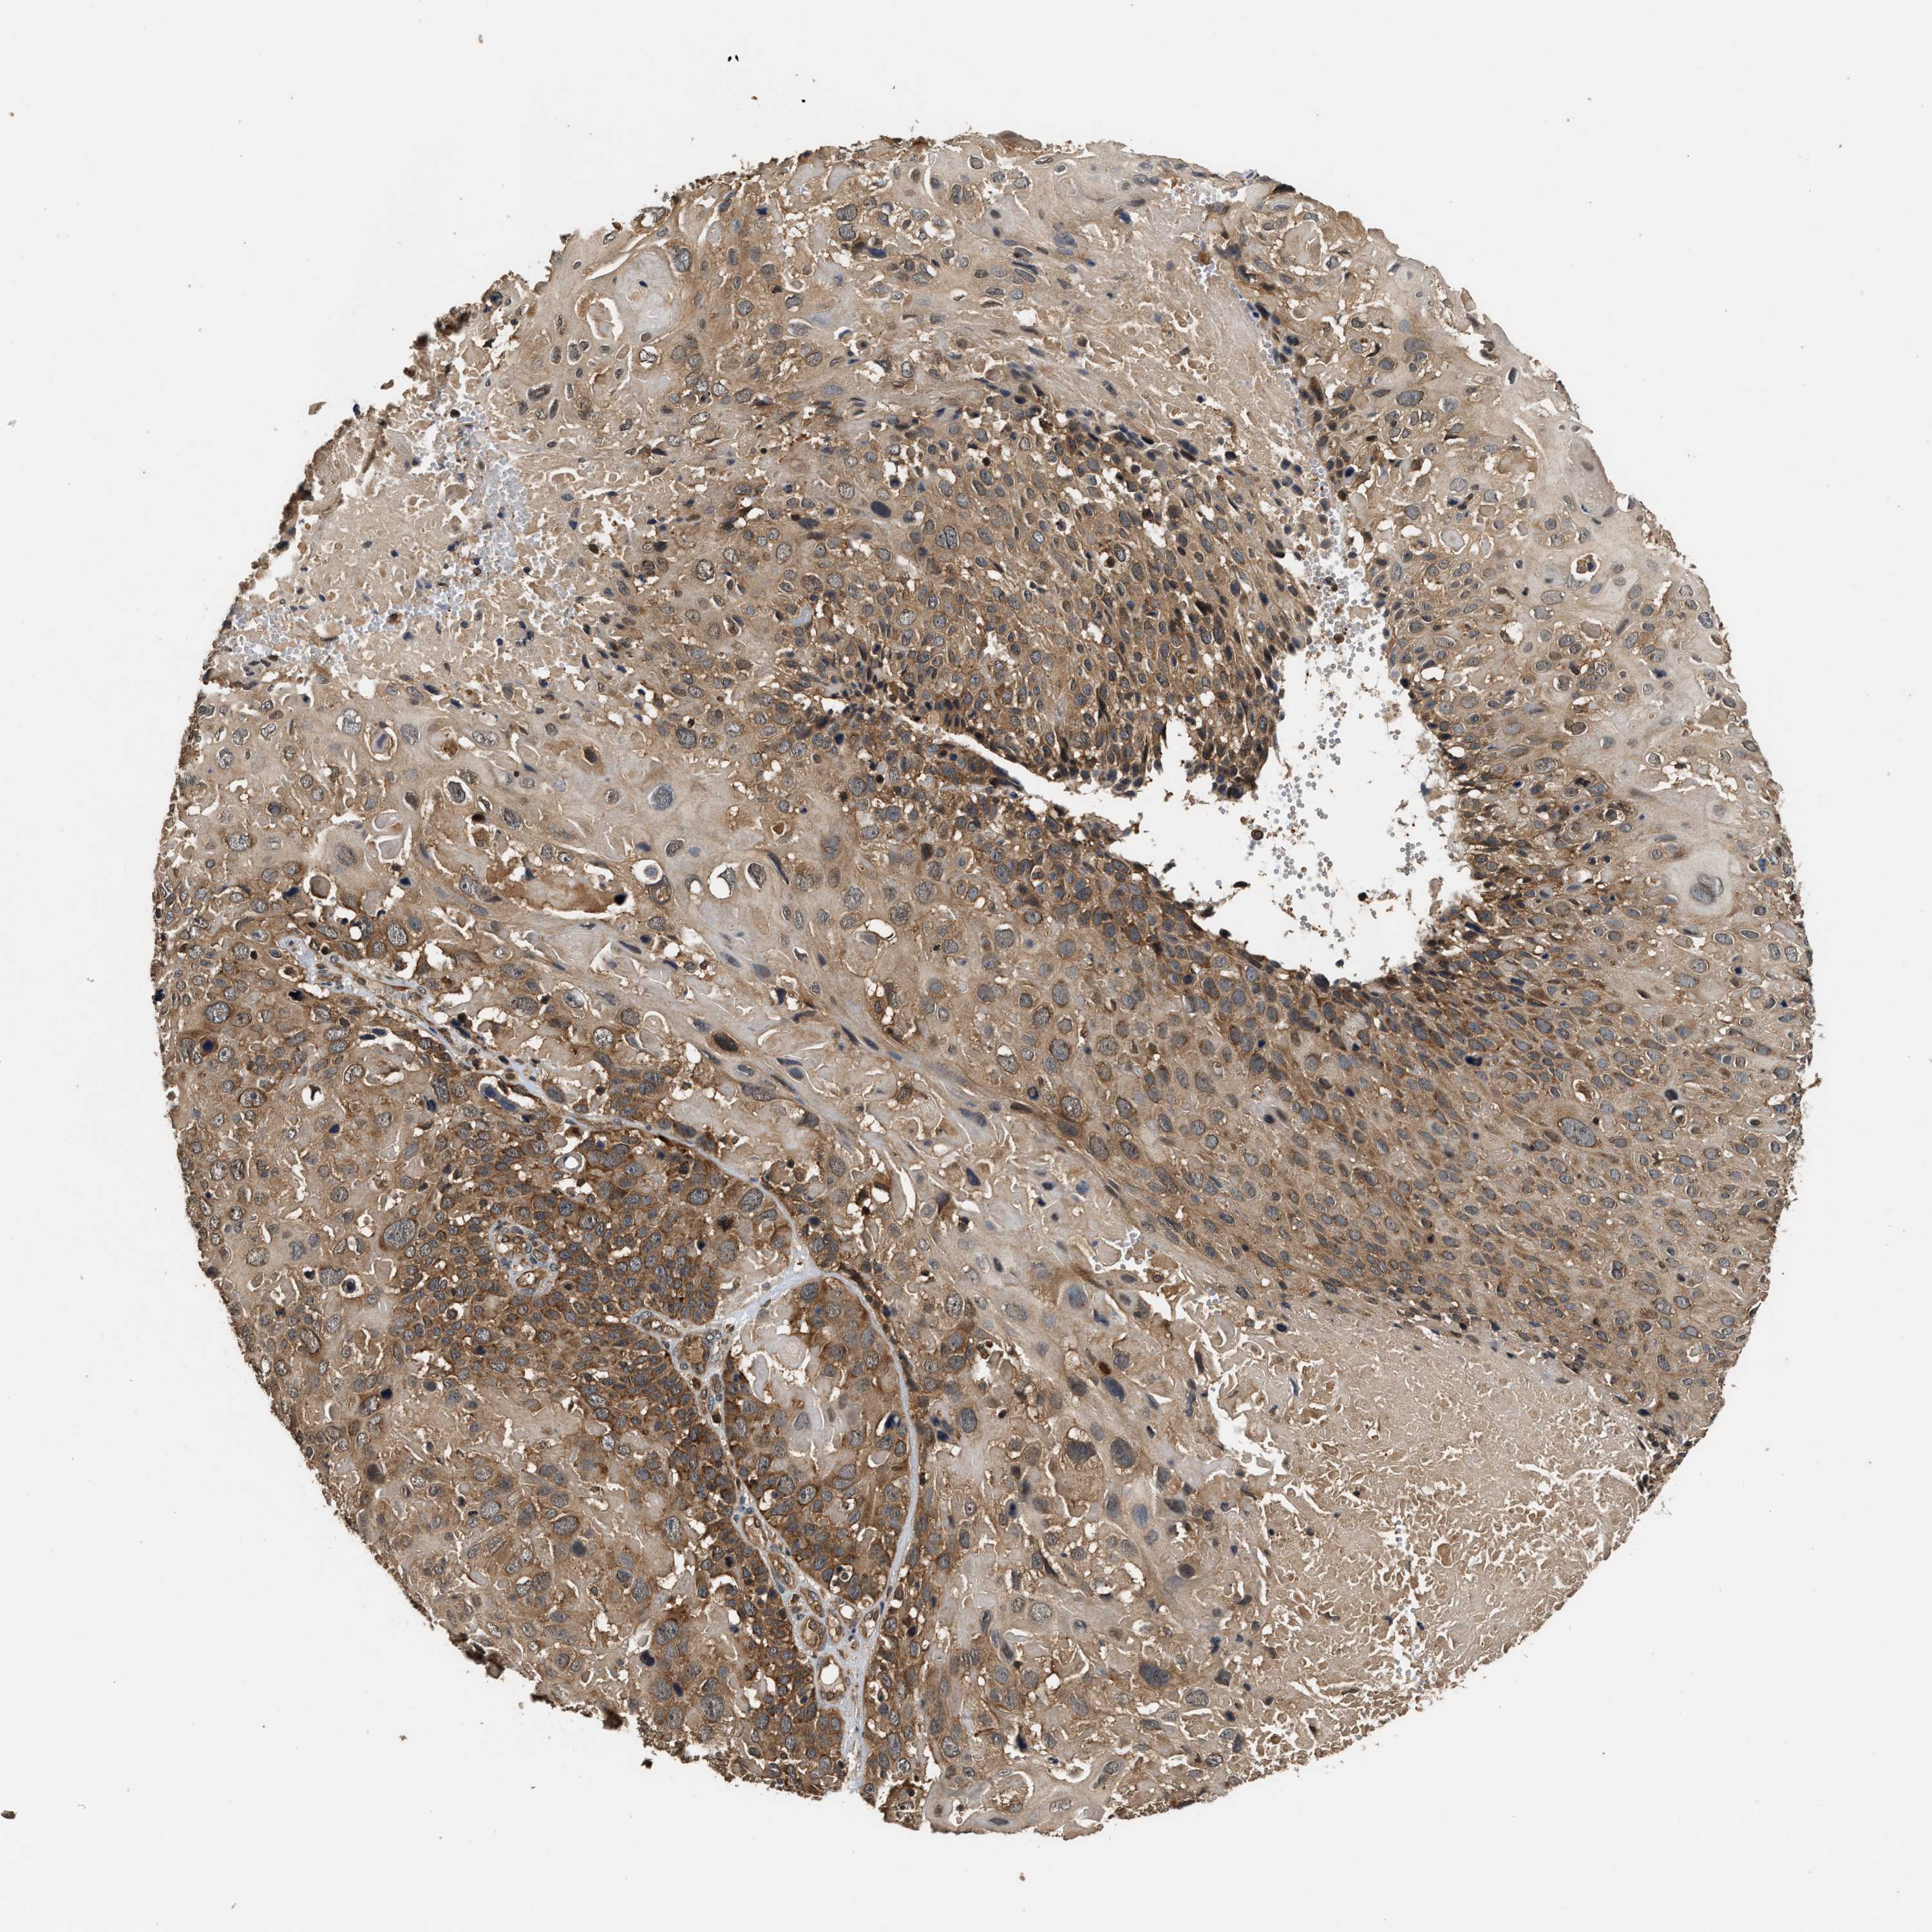

CERVICAL CANCER - Protein expressioni

A mouse-over function shows sample information and annotation data. Click on an image to view it in a full screen mode. Samples can be filtered based on level of antibody staining by selecting one or several of the following categories: high, medium, low and not detected. The assay and annotation is described here.

Note that samples used for immunohistochemistry by the Human Protein Atlas do not correspond to samples in the TCGA dataset.

Antibody stainingi

Antibody staining in the annotated cell types in the current human tissue is reported as not detected, low, medium, or high, based on conventional immunohistochemistry profiling in selected tissues. This score is based on the combination of the staining intensity and fraction of stained cells.

Each image is clickable and will lead to virtual microscopy that enables deeper exploration of all samples and also displays staining intensity scores, fraction scores and subcellular localization as well as patient and tissue information for each sample.

Antibody HPA020454

Staining

High

Medium

Low

Not detected

Intensity

Strong

Moderate

Weak

Negative

Quantity

>75%

75%-25%

<25%

None

Location

Nuclear

Cytoplasmic/membranous

Cytoplasmic/membranous,nuclear

Squamous cell carcinoma, NOS

Adenocarcinoma, NOS